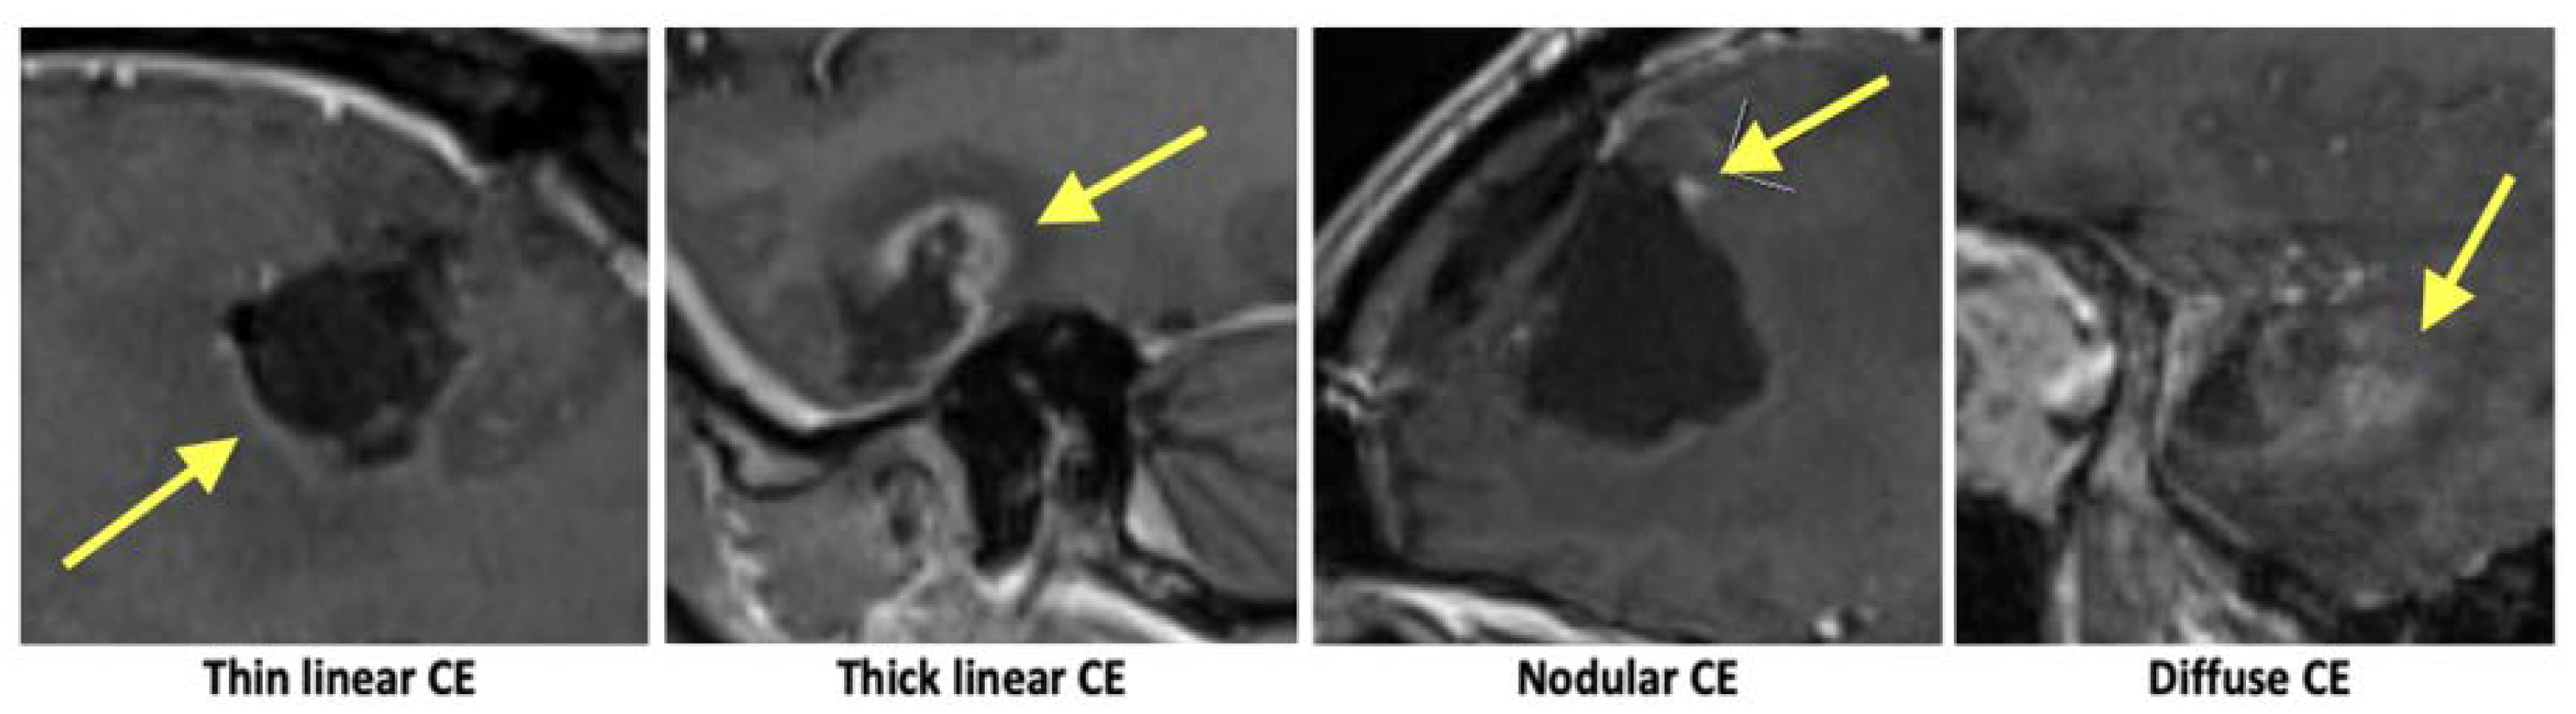

3.2. Contrast Enhancements